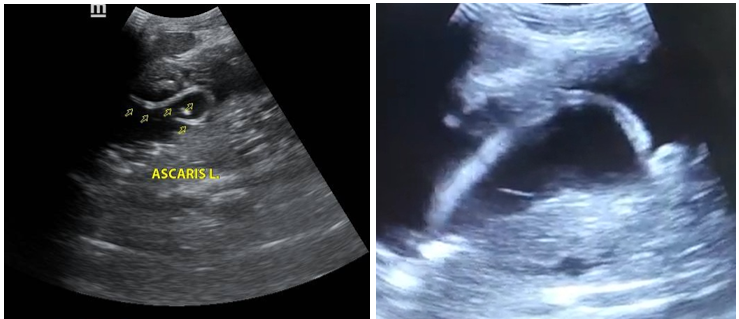

During the real-time evaluation, adult Ascaris worms can be seen curving in the stomach. When the stomach is full of fluid, the Ascaris lumbricoides appears as an echogenic, linear image with linear movement, known as the internal tube sign. Another finding is the spaghetti sign, which is when there is a longitudinal overlap of parasites in the bile duct due to the coiling of one or more Ascaris. The streak sign is a thin streak without an internal tube. The bull's eye sign implies coiling of the parasite. Its motility can be observed on real-time ultrasound. (figure 1A - 1B).

Figure 1. A: Gray scale ultrasound, sagittal section, showing a linear, tubular echogenic image, bull's eye sign. B: Ultrasound shows the sign of the line, which is a thin line without an internal tube and without acoustic shadowing